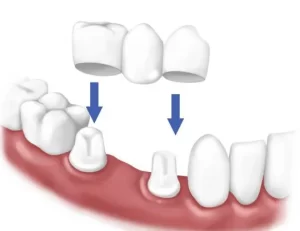

- Support for dental bridges: Crowns are often placed on teeth adjacent to gaps to support a bridge.

Tooth caps and dental crowns are terms that are often used interchangeably, but they have subtle differences. A tooth cap typically refers to a covering that is placed over a tooth, which is understood to have a more temporary or less extensive application than a dental crown. While dental crowns are custom-made to encase the entire tooth and are generally more robust, tooth caps might not offer the same level of protection or aesthetic enhancement.